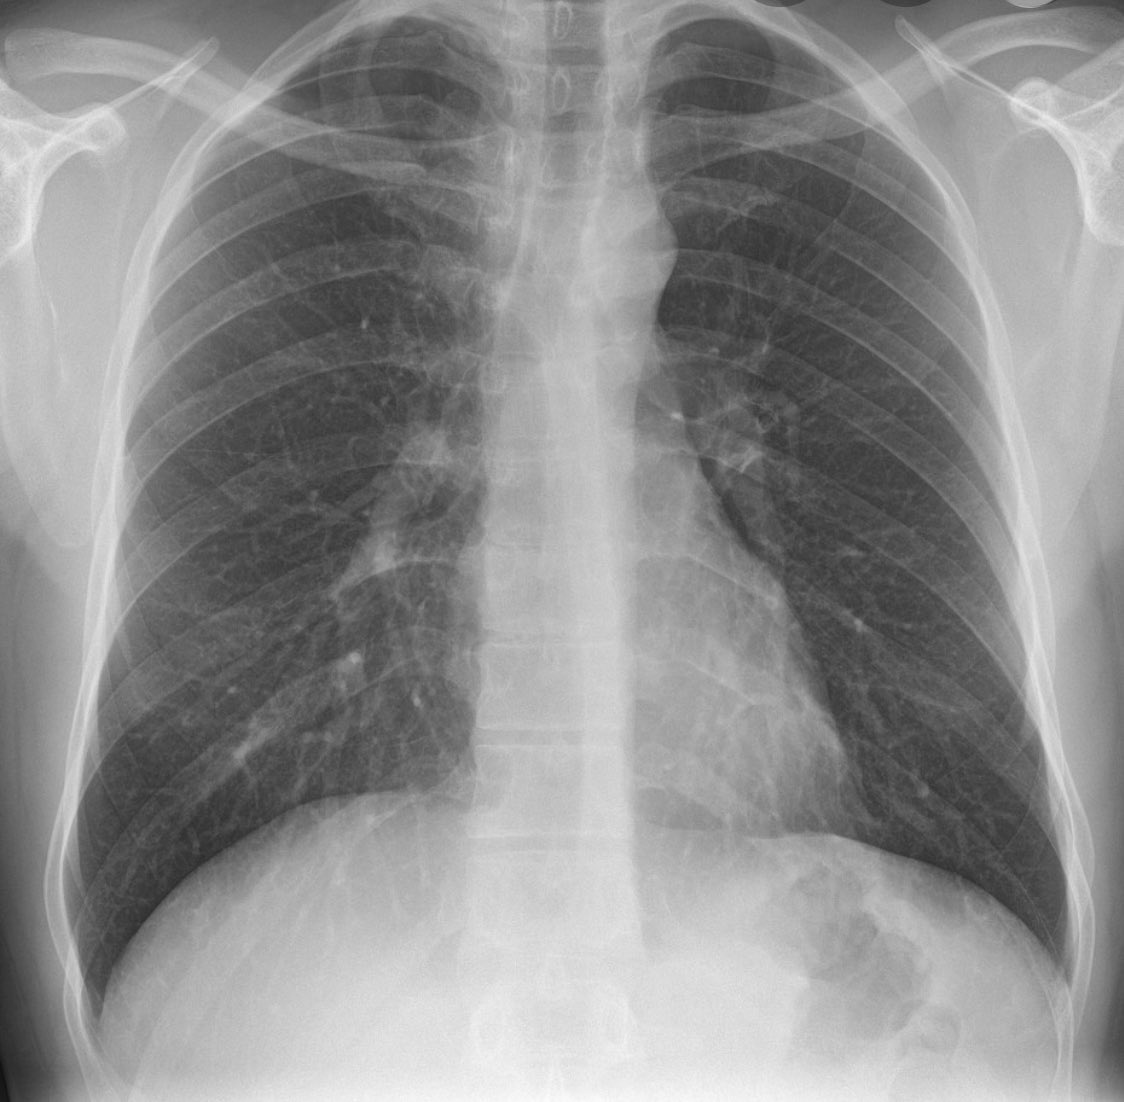

ثالثاً والأهم "أشعة الصدر" chest x-ray

لنحدد هل نزل الالتهاب على الصدر و ما هي حدته.

تنقسم الرئة لجزء أيمن يُقسم بدوره إلى فصين وأيسر يُقسم إلى ثلاثة فصوص ، كوفيد غالباً يبدأ التهابه من "الأطراف/الأضلاع" في الفصوص السفلية من الرئة وغالباً في الجهتين

هذه صور لأشعة صدر طبيعية ( سوداء والقلب في المنتصف ) وأشعة صدر غير طبيعية ، البياض الذي ترونه في الصور الأخرى هو الالتهاب ودرجاته تختلف بالطبع ، كم فص من الرئة أصيب ؟ وماهي الوظائف الحيوية للمريض وقتها و فحوصاته الأخرى